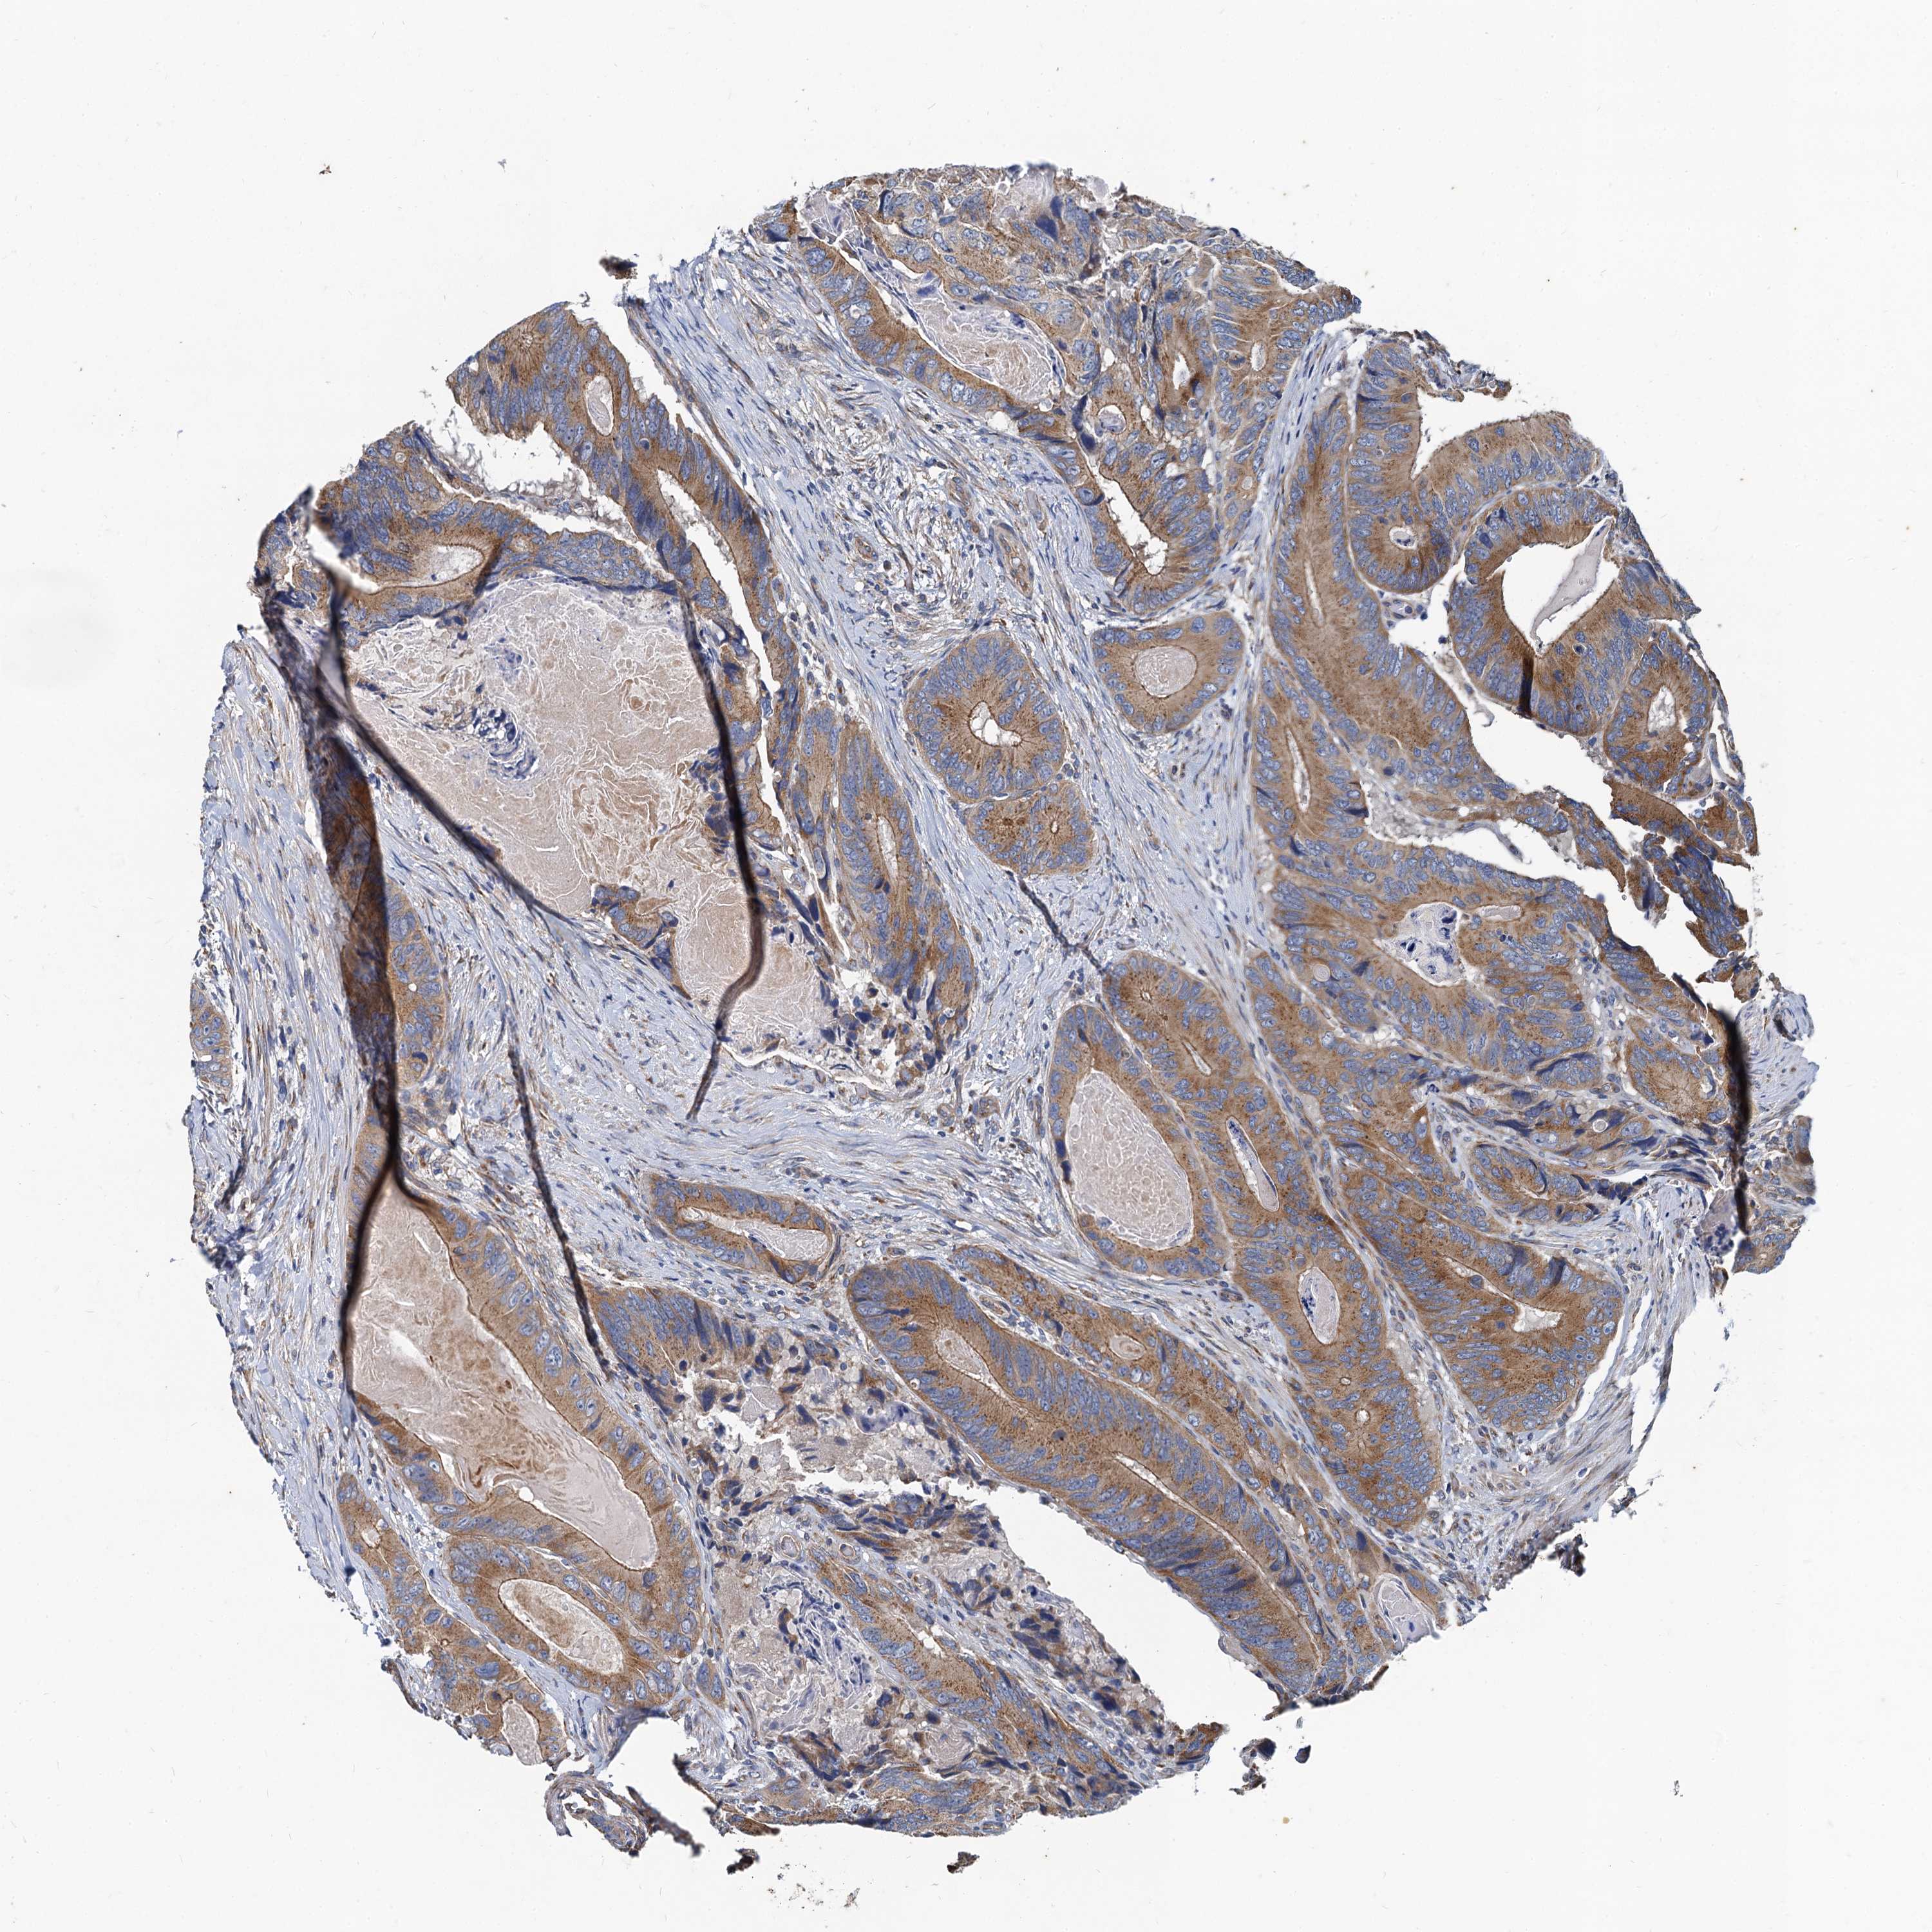

CANCER COLORECTAL CANCER Show tissue menu

Colorectal cancer

Human cancer

Colon adenocarcinoma

Rectum adenocarcinoma